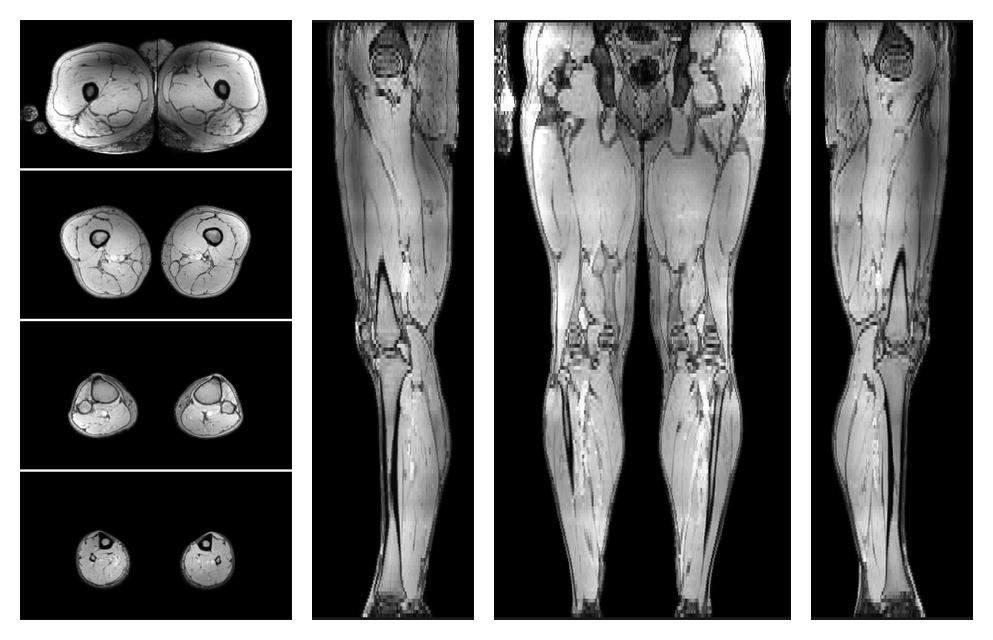

• Automated muscle and bone segmentation.

Overlay of automated muscle segmentation labels on dixon water image.